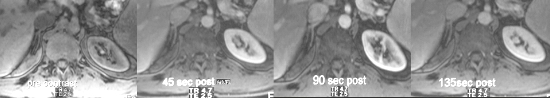

The above images are fat suppressed T1-weighted fat suppressed images of the right adrenal gland. Note the progressive and rapid gadolinium enhancement of the right adrenal gland. In this case, the adrenal gland enhances to the same extent as the spleen and slightly less than the kidneys. Courtesy of: Ashley Davidoff, M.D. |